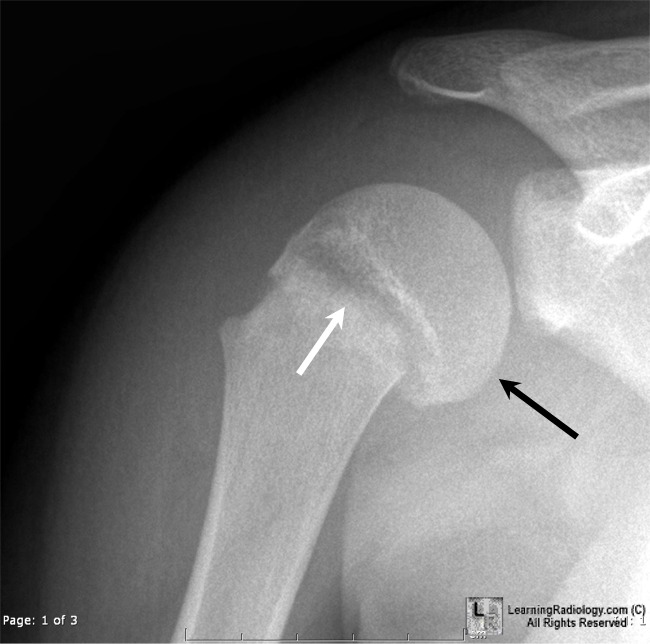

From www.learningradiology.com

LearningRadiology Growth Plate Fracture X Ray Doctors diagnose growth plate injuries by: Joy english, professor of orthopedics, who says a growth plate fracture is common among children and teens and may not always be. Tom miller speaks with dr. The image appears to be that of a healthy knee with no abnormalities because the fracture was exclusively. These should be taken in at least 2. Asking. Growth Plate Fracture X Ray.